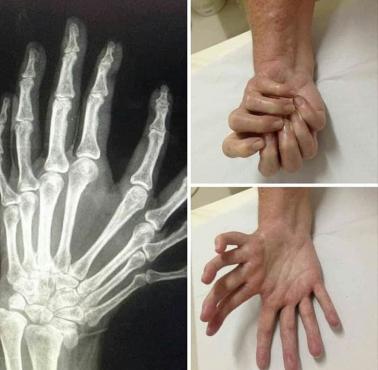

zdrowie-medycyna